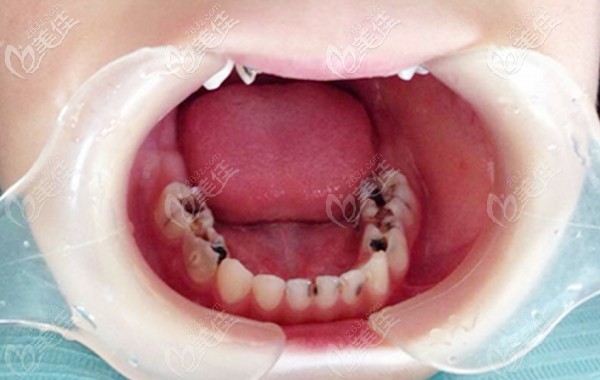

千萬別等到孩子牙齒發(fā)黑或疼痛才開始看牙醫(yī),否則多花錢還遭罪! b1505 G0 V0

家長朋友們:千萬別等到我們寶貝的牙齒發(fā)黑、蟲牙齲齒、牙齒疼痛時,才想起看牙醫(yī),此時只會多花錢還遭罪!

前幾天收到一位寶媽的求助:自家10歲孩子的蛀牙已經爛空了,不知道怎么辦。小編想說,要是大家都知道兒童換牙的順序和年齡,到時間就不會這么慌亂了吧。

五六歲兒童乳牙齲齒需要盡快治療嗎?這些利弊你一定要知道!

五六歲兒童乳牙齲齒需要盡快治療嗎?當然了,因為不及時治療乳牙齲壞很容易壞到牙髓腔,影響恒牙萌出,導致牙齒擁擠不起,這些弊端大家一定要明白!

只因乳牙壞了沒治療,12歲小姑娘花16萬做了下頜骨切除 b1589 G0 V0

經常聽身邊的老人說乳牙壞了不用管,等換完牙就好了,但真的是這樣嗎?前幾天在網上傳出了一個案例,我們一起來看看。